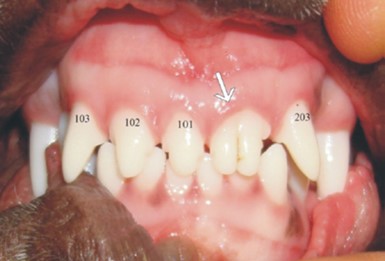

aus: Developmental Structural Tooth Defects in Dogs - Experience From Veterinary Dental Referral Practice and Review of the Literature. Boy S, Crossley D, Steenkamp G. Front Vet Sci. 2016 Feb 8;3:9. doi: 10.3389/fvets.2016.00009. eCollection 2016. Review.)

Zwillingszahn aus einem Zahnkeim

(aus: Developmental Structural Tooth Defects in Dogs - Experience From Veterinary Dental Referral Practice and Review of the Literature. Boy S, Crossley D, Steenkamp G. Front Vet Sci. 2016 Feb 8;3:9. doi: 10.3389/fvets.2016.00009. eCollection 2016. Review.)